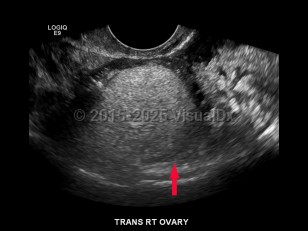

Ovarian cysts

Ovarian cysts are most commonly asymptomatic and diagnosed incidentally on physical exam or imaging. Sometimes the patient with an ovarian cyst may present with acute or chronic abdominal pain.

Depending on the underlying etiology, an ovarian cyst might develop slowly or rapidly. Rapidly forming cysts may be more likely to cause pain. Ovarian cysts, especially functional or physiologic cysts, often resolve spontaneously.